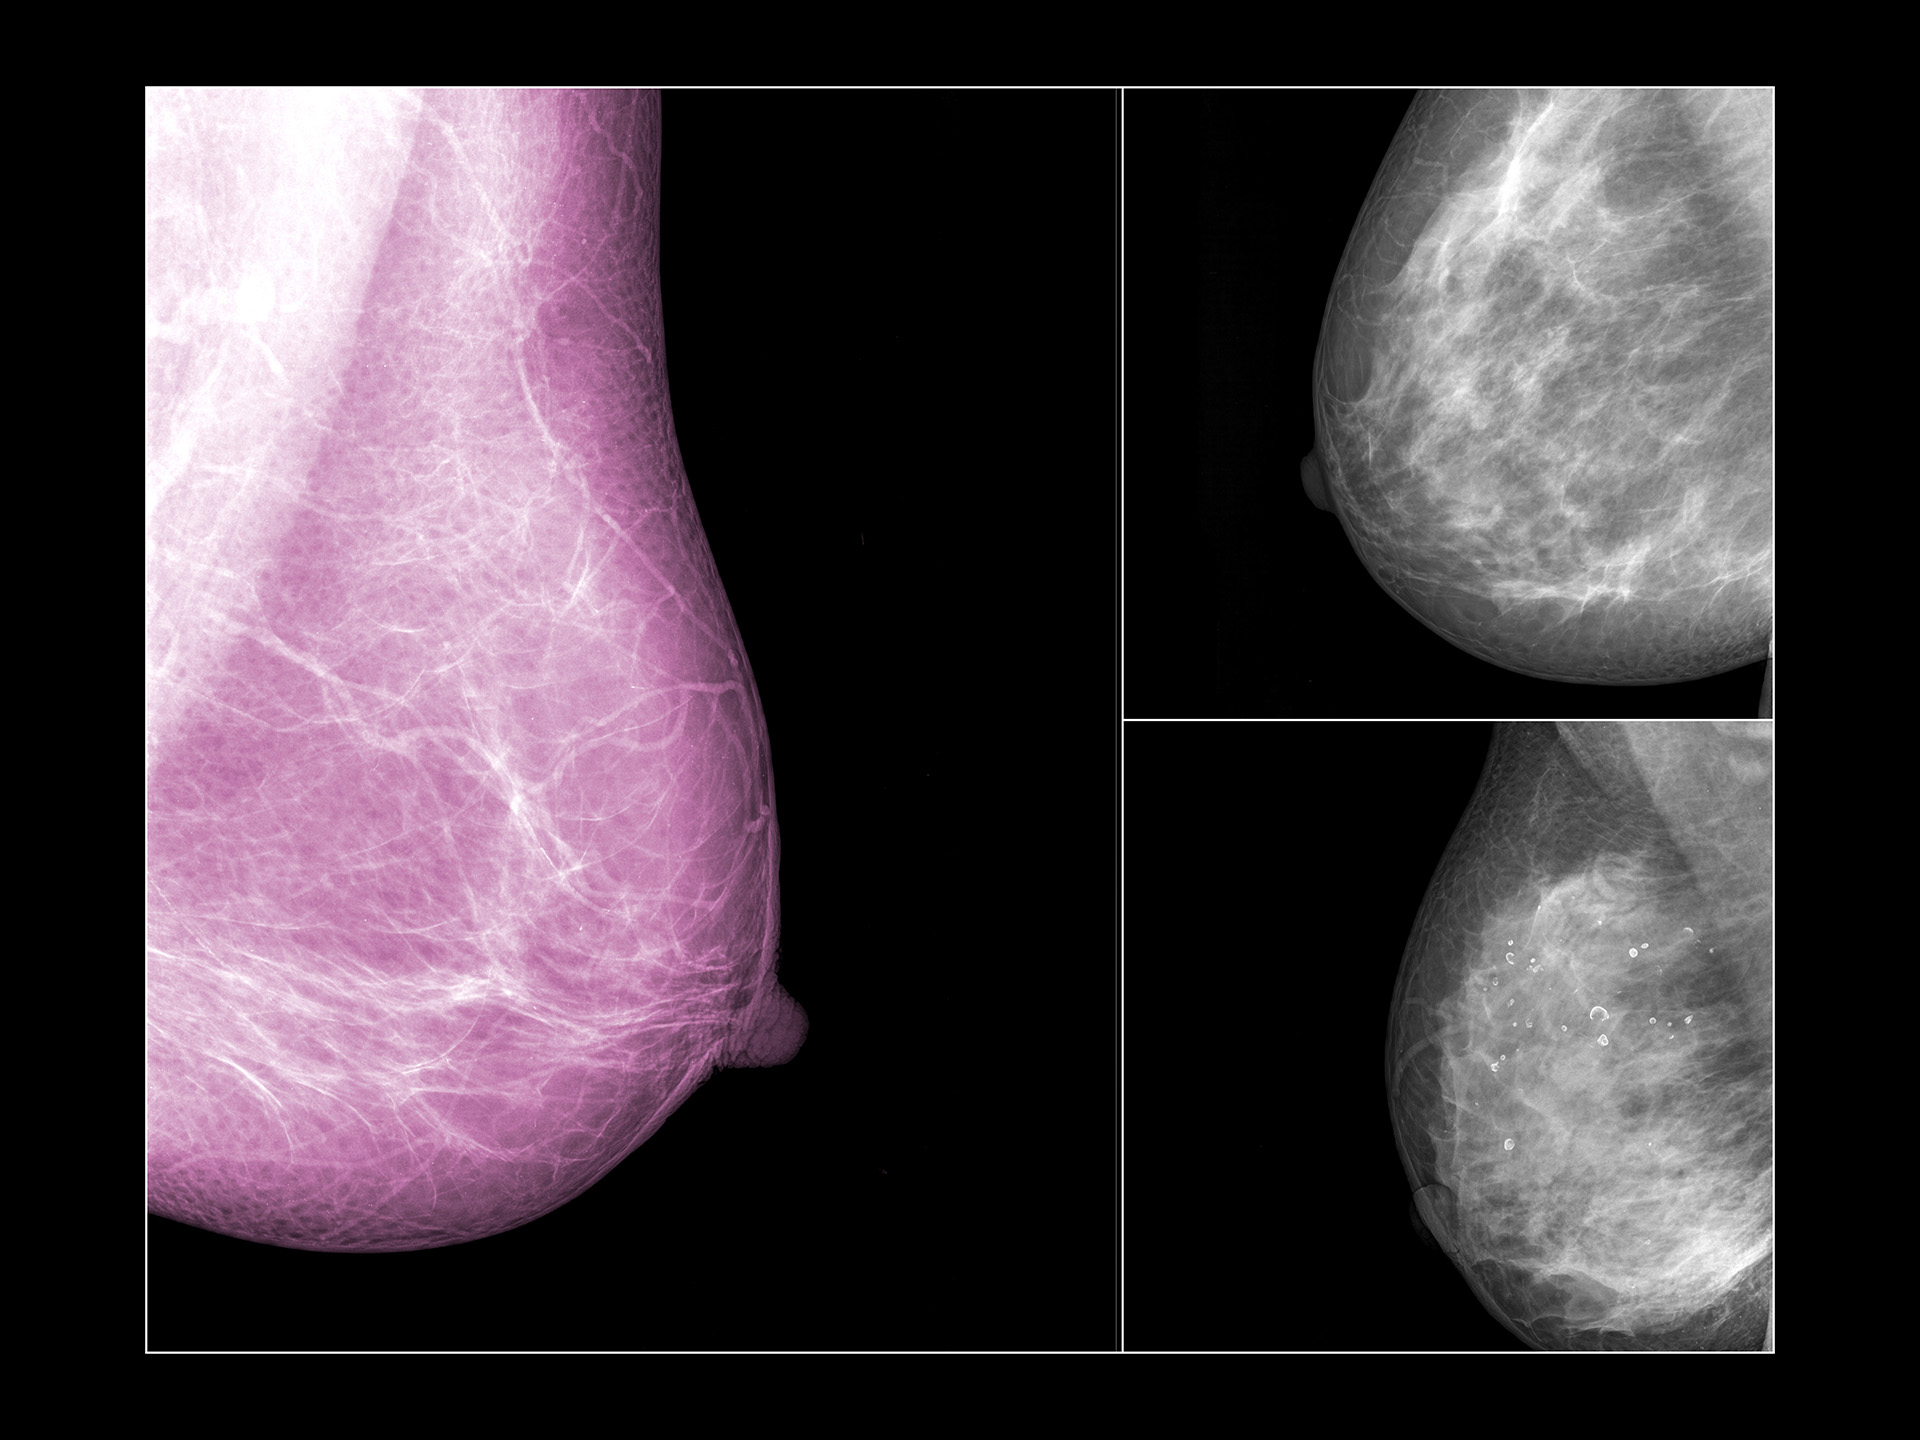

미국 오하이오주립대 암센터(OSUCCC)가 최근 AI를 이용해 소엽성 유방암(lobular breast cancer) 위험을 조기 예측하는 연구를 진행 중입니다. 소엽성 유방암은 유방 안쪽의 젖샘 소엽(lobule), 즉 모유를 만들어내는 부위에서 시작되는데요. 가장 흔한 유형인 유관암(ductal carcinoma)과 달리 소엽성 유방암은 세포가 줄처럼 퍼져 자라기 때문에 종양 덩어리 형태로 나타나지 않는다고 해요. 이 때문에 조기 발견이 어렵고, 발견 시점에는 이미 다른 장기로 전이됐을 가능성도 있다고요. 실제로 미국에서는 전체 유방암의 약 15%를 차지하며, 재발 시 생존율이 더 낮다고 하는데요. 특히 미국의 40세 이상 여성의 약 40%는 치밀 유방(dense breast)을 갖고 있어 방사선 촬영으로는 암을 구분하기가 쉽지 않은 실정입니다. 이에 오하이오주립대 암센터 연구팀은 디지털 병리 이미지와 AI 모델을 결합해 환자의 임상 데이터 속 생체표지를 분석하는 방법을 찾고 있어요. 이렇게 얻은 정보를 토대로 향후 10년 내 암 재발 확률을 예측하는 점수 시스템을 개발 중이죠. “재발 위험이 높은 여성을 미리 찾아내면, 더 면밀하게 관찰하고 치료 전략을 세울 수 있다”는 게 연구진의 설명. 하지만 한계도 있습니다. 응급의학 전문의이자 AI 연구자인 하비 카스트로 박사는 현지 언론을 통해 “AI가 오래된 데이터에 훈련되면 오늘의 패턴을 놓친다”고 지적했어요. 의료 데이터의 시간차, 인종과 연령에 따른 영상 차이를 모두 고려해야 한다는 뜻이죠. 그럼에도 불구하고 유방암의 위험을 미리 예측하는 데 조금이라도 가까워질 수 있다면 그 자체만으로도 유방암 환우들에게 큰 위안이 될 겁니다.